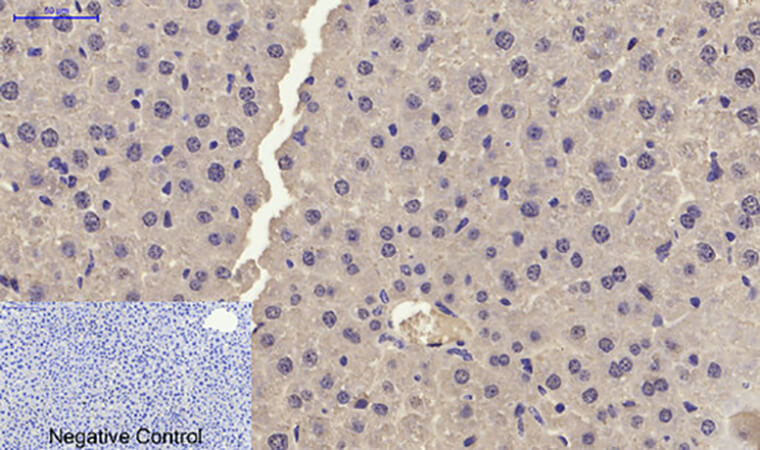

For Immunohistochemistry (IHC) on FFPE sections: Antigen retrieval is non-negotiable—use citrate buffer (pH 6.0, 20 min, 95°C) to unmask the N-terminal epitope. Dilute 1:500 (overnight at 4°C) and pair with a polymer detection kit (e.g., Abbkine’s KTD3010). In p21 IHC for prostate cancer, expect strong nuclear staining in high-grade tumors (Gleason score ≥8); counterstain with hematoxylin to highlight basal cell layers. Funny enough, a lab fixed “no signal” in mouse liver by realizing their sections were over-fixed (24 hrs in formalin vs. 12)—ABP0108 hates excessive crosslinking!